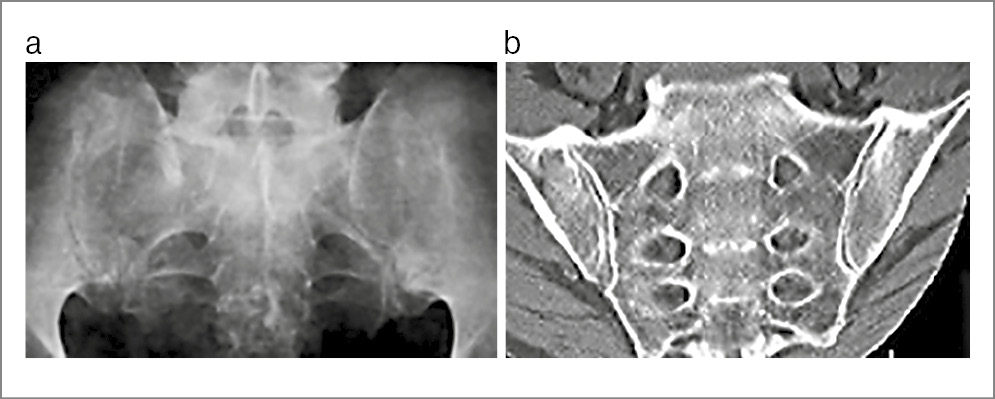

Пациентка В. 29 лет направлена на консультацию в 2023 г. с подозрением на АС. Жалобы на боли в нижней части спины и ягодиц, которые впервые остро возникли на 9-м месяце беременности (за 4 года до настоящей консультации), были стойкими и очень интенсивными. По результатам МРТ (рис. 1) сделано заключение о наличии сакроилиита. После родов боли продолжались, но постепенно стали менее сильными и непостоянными. Скорость оседания эритроцитов и уровень СРБ не повышались. Обнаружен HLA-B27. Установлен диагноз АС. Во время осмотра пациентки осанка существенно не нарушена, движения в позвоночном столбе не ограничены и безболезненны, болезненность при пальпации гребня левой подвздошной кости и в проекции левого КПС. Пересмотр МРТ четырехлетней давности позволил обнаружить стресс-переломы крестца с обеих сторон и массивный отек костного мозга вокруг линий переломов. Повторное МРТ-исследование (2023 г.) показало, что отек костного мозга в крестце отсутствует. На рентгеновском снимке признаков сакроилиита, нарушений целостности крестца не найдено. Рентгеноостеоденситометрия: показатели минеральной костной плотности в поясничном отделе позвоночника и проксимальном отделе бедренной кости в норме. Предположение об АС отвергнуто, установлен диагноз заживших (заживающих?) стресс-переломов крестца.

Рис. 1. Пациентка В. 29 лет. Стресс-переломы крестца, развившиеся на 9-м мес беременности. МРТ (коронарная проекция, режим STIR): в обеих боковых массах крестца отмечаются обширные зоны сигнала повышенной интенсивности (отек костного мозга), на фоне которого прослеживаются линии переломов (указаны стрелками).